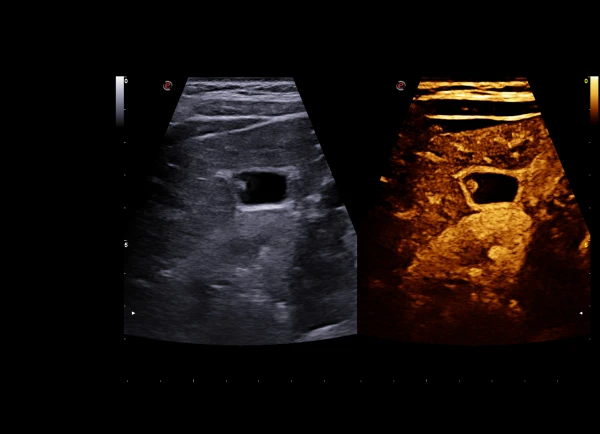

Ultrasonik nurlanishni shakllantirish (XPower Beamforming) va ma'lumotlarni qayta ishlashdan keyingi ishlov berish (XSmart Postprocessing) uchun zamonaviy texnologiyalarning kombinatsiyasi ultra sifatli tasvirni yaratishga imkon beradi.

Qurilmaning kuchli grafik protsessori ma’lumotlar uzatish tezligini to‘rt baravar tezlashtiradi, bu esa bir necha rejimlarda tekshiruvlar o‘tkazish imkonini beradi va skanerlashning jonli efirini ta’minlaydi.